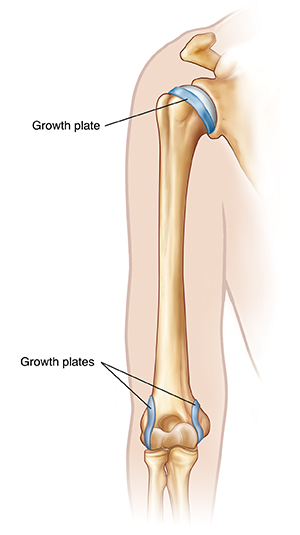

Your child has been diagnosed with little leaguer’s elbow or shoulder. Little leaguer’s elbow or shoulder is caused by overuse of the arm. This condition is an irritation of the growth plates in the elbow or shoulder. A growth plate is the soft part of a bone that lets the bone grow as the child grows. Little leaguer’s elbow or shoulder is most common among children who play sports, especially baseball. Because a child is still growing and developing, the demands of a sport on the child’s body can be too much. This is especially true if the child isn’t given enough rest time between active sessions. Little leaguer’s elbow or shoulder is a painful condition. But it can be treated with correct care.

Little leaguer’s elbow or shoulder is caused by too much overhead movement of the arm, such as pitching a baseball. Overhead movement causes the muscles in the arm to pull on the growth plates. When this movement is repeated over and over, the space in the growth plates begins to get wider. In some cases, the growth plates pull away from the bone.